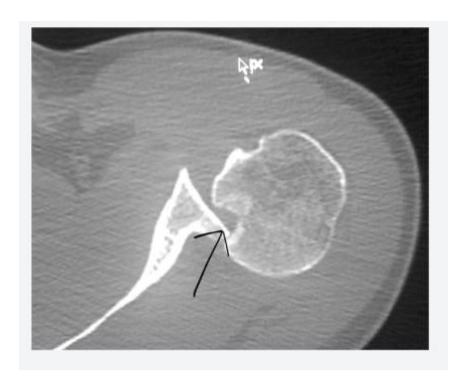

Hill-Sachs Lesion

What does this photo show?

- Hill-Sachs lesion

18-year-old male presented after sport injury and unable to do internal rotation of right shoulder. What is the name of the injury seen in the figure?

- Hill-Sachโs defect

18-year-old male presented after sport injury and unable to internally rotate his left shoulder. What is the diagnosis?

A case scenario about a male with anterior shoulder dislocation. What does the figure 1b show?

reverse - Hill sachs lesion

What do you see in this image?

- Hill sachs lesion